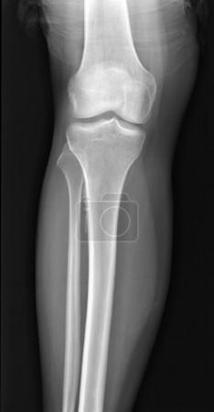

ЯК НАЗИВАЄТЬСЯ ЦЯ КІСТКА?

варіанти відповідей

FIBULA

TIBIA

HUMERUS

RADIUS

ULNA

РОЗПІЗНАЙТЕ КІСТКУ ТА ЇЇ ЧАСТИНУ, ЯКУ ВИ ЛЕГКО МОЖЕТЕ ПРОПАЛЬПУВАТИ У СЕБЕ.

ПЕРЕДНІЙ ГОСТРИЙ КРАЙ

12

13

ГОРБИСТІСТЬ

МЕДІАЛЬНА КІСТОЧКА

ГОЛОВКА